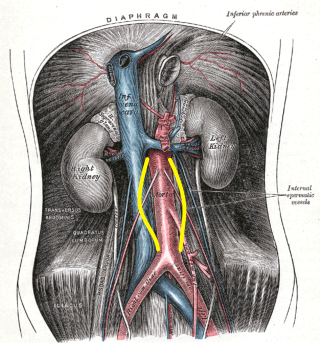

A causa delle leggi fisiche dei fluidi, la tensione che si produce sulla parete di un'arteria ad ogni gettito cardiaco è proporzionale al diametro del vaso oltre che alla pressione. Avendo l'aorta un grosso calibro, l'ipertensione è deleteria in modo particolare su una parete vasale resa anelastica e più soggetta allo sfiancamento. All'assottigliamento dovuto ai processi sopra accennati, si aggiunge infatti l'esito dei meccanismi riparativi spontanei, che cercano di rimpiazzare le fibre elastiche danneggiate ad esempio dai depositi di grassi, con del nuovo materiale che però è fibroso, rigido. Le altre malattie causa di aneurisma aortico possono essere la sifilide, molto meno frequente che in passato, la tubercolosi, le infezioni batteriche, l'artrite reumatoide. Infine esistono gli aneurismi congeniti, associati a malattie delle valvole cardiache. Gli aneurismi aortici da arteriosclerosi aterosclerotica, si formano prevalentemente nel tratto addominale a valle delle arterie renali.

A causa delle leggi fisiche dei fluidi, la tensione che si produce sulla parete di un'arteria ad ogni gettito cardiaco è proporzionale al diametro del vaso oltre che alla pressione. Avendo l'aorta un grosso calibro, l'ipertensione è deleteria in modo particolare su una parete vasale resa anelastica e più soggetta allo sfiancamento. All'assottigliamento dovuto ai processi sopra accennati, si aggiunge infatti l'esito dei meccanismi riparativi spontanei, che cercano di rimpiazzare le fibre elastiche danneggiate ad esempio dai depositi di grassi, con del nuovo materiale che però è fibroso, rigido. Le altre malattie causa di aneurisma aortico possono essere la sifilide, molto meno frequente che in passato, la tubercolosi, le infezioni batteriche, l'artrite reumatoide. Infine esistono gli aneurismi congeniti, associati a malattie delle valvole cardiache. Gli aneurismi aortici da arteriosclerosi aterosclerotica, si formano prevalentemente nel tratto addominale a valle delle arterie renali.

L'aneurisma aortico può essere evidenziato radiologicamente se nel suo contesto è presente del calcio che permette la visualizzazione del contorno dell'aneurisma stesso. Bisogna tuttavia ricordare che molti aneurismi non mostrano calcificazioni, pertanto la presenza dell'aneurisma sfugge all'esame radiologico diretto dell'addome. L'ecografia permette di visualizzare accuratamente l'aneurisma ed identificare l'eventuale presenza di un trombo adeso alla parete, lo stesso esame permette di seguire l'evoluzione dell'aneurisma stesso, la sua eventuale progressiva dilatazione, permettendo un approccio chirurgico tempestivo, non con caratteristiche di urgenza e quindi con elevata sopravvivenza post intervento. L'aortografia è una tecnica diagnostica invasiva che spesso si esegue in previsione di un intervento chirurgico. Altre tecniche non invasive per la diagnosi sono la TC e la MRI.